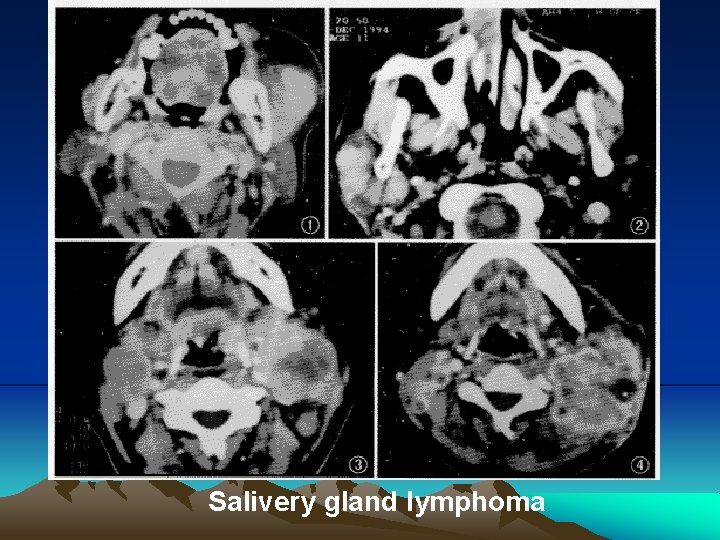

Salivery gland lymphoma: Multiple maxillofacial extranodal sites of soft tissue mass with the presence of non-necrosis and uneven margin should be considered as the characteristic sign of NHL disease in the head and neck

Salivery gland lymphoma